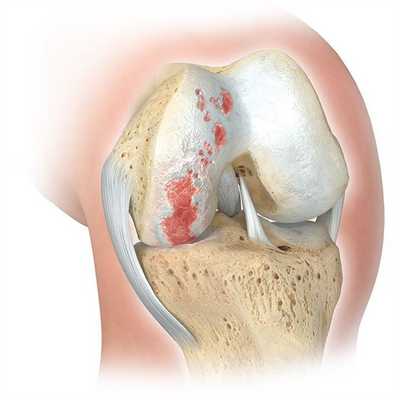

Переломы проксимального отдела большеберцовой кости - достаточно распространенное явление, сопровождающееся повреждением преимущественно латерального мыщелка с частичным или полным разрывом соответствующего мениска. Авторами разработан фиксатор для накостного остеосинтеза. Фиксатор является индивидуальной анатомической премоделированной пластиной. Проведено исследование, в котором приняли участие пациенты с переломами проксимального отдела большеберцовой кости. Достигнуты положительные результаты в 96,7% случаев, из них хорошие результаты наблюдались в 73,3%, удовлетворительные результаты в 23,4%, неудовлетворительные результаты отмечались у 3,3% от всей группы пациентов.

Переломы проксимального отдела большеберцовой кости относятся к тяжёлым повреждениям нижних конечностей и составляют от 6,5 до 12% всех внутрисуставных переломов коленного сустава и 7% от всех переломов опорно-двигательного аппарата [1, 4]. Внутрисуставные переломы являются результатом осевой нагрузки в сочетании с некоторой варусной и вальгусной силой [13]. Подобные переломы проксимального отдела большеберцовой кости характеризуются сложностью восстановления функции коленного сустава, что приводит к стойкой инвалидизации пациента [3, 5]. За последнее десятилетие число осложнений выросло на 20-40%, а процент больных, получивших инвалидность в результате неполностью восстановленной функции коленного сустава, составляет 5,9 - 9,1% [2, 14]. Развитию осложнений частично способствует несвоевременная диагностика данных повреждений [11, 12]. Рентгенологическое исследование и КТ-исследование поврежденного сустава уже вошло в стандарт предоперационного планирования [9, 10, 15]. Именно поэтому адекватная диагностика и своевременное лечение перелома проксимального отдела большеберцовой кости представляет собой актуальную задачу.

Целью лечения таких переломов является анатомическое восстановление суставной поверхности, профилактика посттравматического дегенеративного заболевания сустава, устойчивый остеосинтез, позволяющий раннюю мобилизацию [7, 8]. Выбор лечения зависит от возраста пациента, его состояния, конфигурации перелома, степени смещения отломков и состояния поверхностных мягких тканей, связанных с костными повреждениями и любыми нейроваскулярными осложнениями [6].

Анализ локализации переломов выявил: в 10 случаях повреждение латерального мыщелка большеберцовой кости, что составило 55,6% от всего количества больных, принявших участие в исследовании. В 3 случаях было диагностировано повреждение медиального мыщелка без повреждения медиального мениска, что составило 16,7% от всего количества больных. В 5 случаях был выявлен перелом обоих мыщелков проксимального метаэпифиза, что составило 27,8% от всего количества больных, принявших участие в исследовании, из которых в 2 случаях был выявлен частичный разрыв обоих менисков, в 1 случае частичный отрыв медиального мениска, и в 1 случае диагностирован полный отрыв латерального мениска. При полных отрывах менисков производилась менискэктомия, при частичных отрывах делали порционную резекцию мениска. Как показано в таблице 3, большинство пациентов имели переломы проксимального отдела большеберцовой кости типа В (В1, В2) и типа С (С1, С2).

При поступлении больных с переломами проксимального отдела большеберцовой кости в стационар проводились обследования в соответствии с МЭС 79.100. Выполнялись рентгенограммы в двух проекциях в масштабе 1:1, МСКТи МРТисследования коленного сустава. По данным рентгенограмм в прямой и боковой проекции снимались размеры проксимального метаэпифиза большеберцовой кости. Далее подготавливалась индивидуальная анатомическая премоделированная пластина «Пегас 3 D» (рис 6, 7). Предоперационные рентгенологическое и КТ исследования поврежденных коленных суставов позволили точнее оценить изучаемые структуры коленного сустава, подобрать вид фиксаторов и их размер.

Клинический пример No1

Пациент Б., 65 лет. Травма получена в результате ДТП (пешеход). Первая помощь была оказана по месту травмы. Затем был переведен в ДКБ им. Н.А. Семашко. При поступлении в клинику выполнена рентгенография в двух стандартных проекциях (рис. 8 а, б), КТ-исследования коленного сустава (рис. 9). Поставлен диагноз: «Компрессионный перелом наружного мыщелка большеберцовой кости справа со смещением. Разрыв наружного мениска. Гемартроз». Тип В3 по классификации АО/ASIF. Выполнена операция: открытая репозиция наружного мыщелка правой большеберцовой кости с остеосинтезом наружного мыщелка премоделированной пластиной с частичной резекцией наружного мениска (рис. 10 а, б). Пациенту была установлена одна ветвь фиксатора на латеральный мыщелок (рис. 11 а, б). Послеоперационной иммобилизации не было. Разработка коленного сустава осуществлялась на 2-3 сутки. После полного сращения перелома, через 7 месяцев после установки фиксатора выполнена операция удаления фиксатора (рис.12 а, б). Функция коленного сустава сохранена, сгибание более 600, разгибание 1800 (рис.13 а, б).